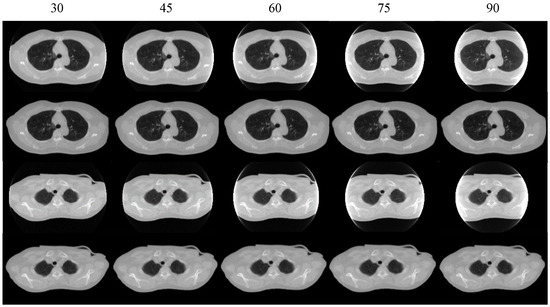

| 30 | 45 | 60 | 75 | 90 | |

|---|---|---|---|---|---|

| MAE (HU) | 24.16 | 22.27 | 19.96 | 35.20 | 70.30 |

| RMSE (HU) | 56.18 | 34.88 | 31.65 | 95.23 | 131.98 |

| SSIM (%) | 98.13 | 98.15 | 98.00 | 96.47 | 94.75 |